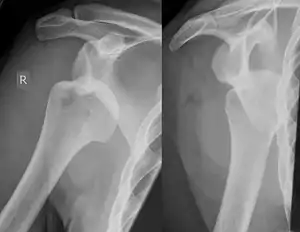

A Hill–Sachs lesion, or Hill–Sachs fracture, is a cortical depression in the posterolateral head of the humerus. It results from forceful impaction of the humeral head against the anteroinferior glenoid rim when the shoulder is dislocated anteriorly.

Diagnosis can be suspected by history and physical examination which is usually followed by imaging. Because of the mechanism of injury, apprehension of anterior dislocation is common with provocative maneuvers. Hill–Sachs lesions have been classified as "engaging" or "non-engaging", with engaging lesions defined by the ability of the glenoid to sublux into the humeral head defect during abduction and external rotation. Engaging dislocations have a higher risk of recurrent anterior dislocation, and their presence can help guide surgical management.[2] Imaging diagnosis conventionally begins with plain film radiography. Generally, anteroposterior (AP) radiographs of the shoulder with the arm in internal rotation offer the best yield while axillary views and AP radiographs with external rotation tend to obscure the defect. However, pain and tenderness in the injured joint make appropriate positioning difficult and in a recent study of plain film x-ray for Hill–Sachs lesions, the sensitivity was only about 20%. i.e. the finding was not visible on plain film x-ray about 80% of the time.[3]

By contrast, studies have shown the value of ultrasonography in diagnosing Hill–Sachs lesions. In a population with recurrent dislocation using findings at surgery as the gold standard, a sensitivity of 96% was demonstrated.[4] In a second study of patients with continuing shoulder instability after trauma, and using double contrast CT as a gold standard, a sensitivity of over 95% was demonstrated for ultrasound.[5] It should be borne in mind that in both those studies, patients were having continuing problems after initial injury, and therefore the presence of a Hill–Sachs lesion was more likely. Nevertheless, ultrasonography, which is noninvasive and free from radiation, offers important advantages.

MRI has also been shown to be highly reliable for the diagnosis of Hill-Sachs (and Bankart) lesions. One study used challenging methodology. First of all, it applied to those patients with a single, or first time, dislocation. Such lesions were likely to be smaller and therefore more difficult to detect. Second, two radiologists, who were blinded to the surgical outcome, reviewed the MRI findings, while two orthopedic surgeons, who were blinded to the MRI findings, reviewed videotapes of the arthroscopic procedures. Coefficiency of agreement was then calculated for the MRI and arthroscopic findings and there was total agreement ( kappa = 1.0) for Hill-Sachs and Bankart lesions.[6]